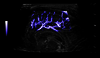

Accurate image quality and non-invasive imaging tools help you deliver fast, confident diagnoses across a wide range of patientsʼ conditions, from neonate cranial scans to abdominal or pelvic pain.

The L6-24-D high-frequency probe provides outstanding detail and clarity for superficial structures, powered by XDclear technology.

LOGIQ Ultrasound, with cSound™ Imageformer, enables delivering images of incredible uniformity from near to far field. Thereʼs no need to manually adjust the focus - the information you need is there, instantly.